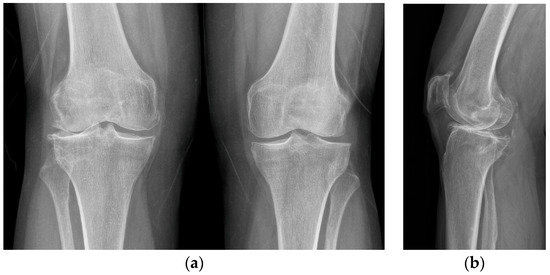

One-Stage Tricompartmental Hypoallergenic UKA for Tricompartmental Osteoarthritis: A Case Report

2. Case Description